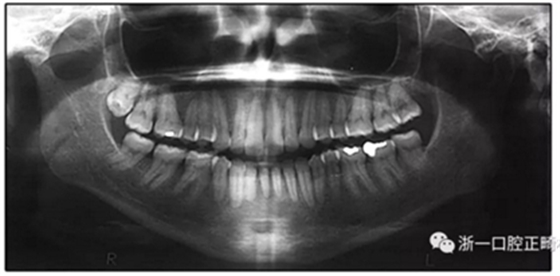

圖3. 治療前頭影側(cè)位片,頭影測(cè)量描跡圖和全口X光片